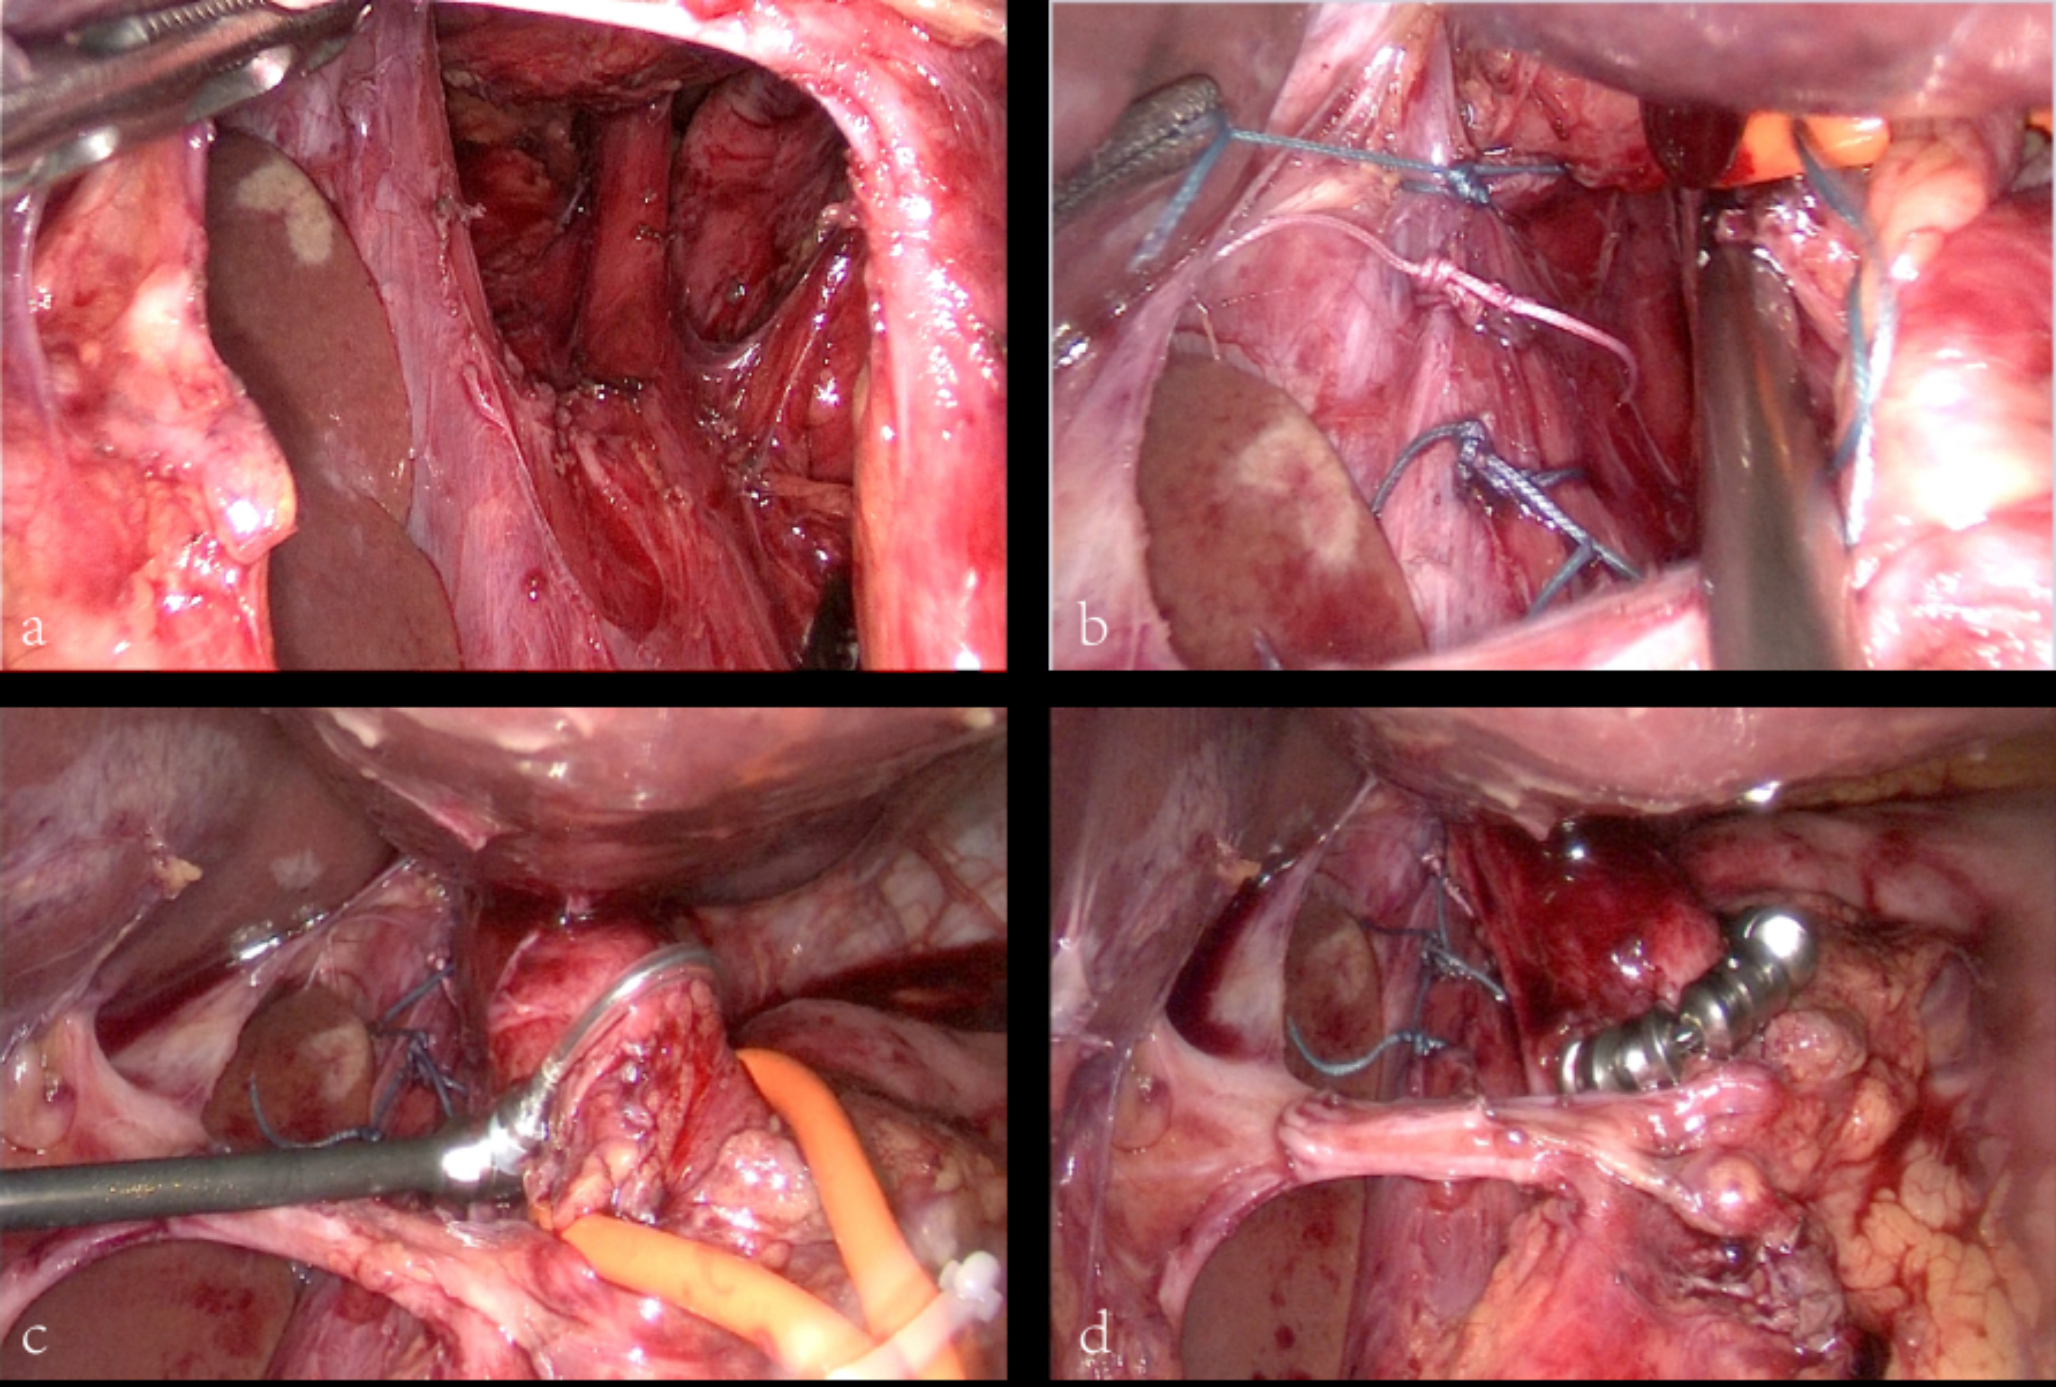

The phrenoesophageal ligament was opened by the surgeon, who also removed the adhesions that were present between the hernial sac and the left crus of the diaphragm. With great care, the pleura was preserved when the abdominal section of the esophagus was circumferentially released up to 5 cm above the diaphragm. The hiatus was then closed using 2 − 0 non-absorbable sutures, leaving only enough space for the esophagus to pass through (Fig. 1a-b).

The esophageal circumference was measured using an esophageal sizing device to determine an appropriate size for the selected MSA device. The sizing device mainly consists of a size indicator, a shaft, and a sizing loop (Fig. 2a). The surgeon passes the handle through the posterior of the esophagus and pushes out the sizing loop, pushing the holder. When the end of the sizing loop with a magnet is combined with the end of the shaft, the holder is pulled back to wrap the sizing loop around the esophagus tightly. There is a scale indicator on the shaft(Fig. 2b), and the surgeon selects the corresponding MSA device based on the indicated value (Fig. 1c-d). No mesh or esophageal bougie was used during the surgery and MSA device placement. For LNF, an absorbable mesh was placed and fixed by sutures. A 360° floppy fundoplication was fashioned over a 44 F bougie using three pledged Ethibond sutures, with the second and third sutures incorporating an esophageal wall.

Fig. 1

Surgical procedures. a: Exposure of the hiatal hernia. b: Repair of the hiatal hernia. c: Measurement of the esophageal circumference. d: Placement of the MSA device